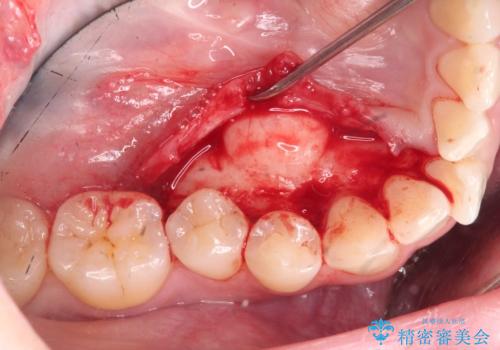

マウスピース矯正前に行う骨隆起の除去

- マウスピース矯正を行うにあたり、舌のスペースが狭くなってしまうことから骨隆起の除去を希望されました。

骨隆起の除去は30分ほどの小手術で終了します。

外科処置の注意事項(リスク・副作用など)

- 外科手術のため、術後に出血、痛みや腫れ、違和感を伴います